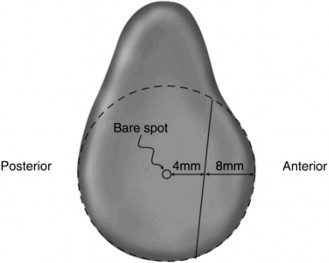

Other normal variants found in the shoulder that should be known include a sublabral foramen (Fig. 2–23A) at about 2 o’clock position on a right shoulder that occurs in about 3.3% of shoulders and a sublabral foramen with a cord-like MGHL that occurs in about 8.6% of shoulders. Another normal variant is a meniscoid superior labrum in which the inner lip of the labrum partially covers the glenoid articular cartilage. True SLAP tears can be differentiated from these normal variants because they show hemorrhage or granulation tissue at the base of the biceps tendon or under the labrum, and there is a space between the glenoid articular cartilage and the superior labrum/biceps tendon that can be mobilized 3 to 4 mm with traction of the biceps tendon. Objectives: Did you learn...? Diagnose a SLAP tear through imaging? Classify SLAP tears?